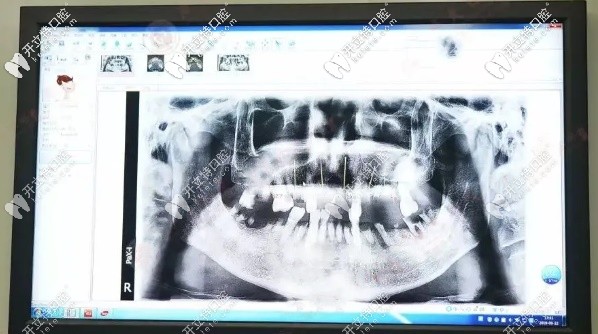

爺爺歲數(shù)大了,牙齒隨著年齡增長也在松動脫落再加上之前也沒有重視過刷牙的問題,也從來沒注意口腔健康。造成現(xiàn)在能用的牙齒幾乎沒有,連吃飯都成了問題,更別說吃肉了,長此以往,營養(yǎng)跟不上,心情也不好了,那段時間見到爺爺都瘦了好多,這樣下去情況很糟。牙齒拍的片子